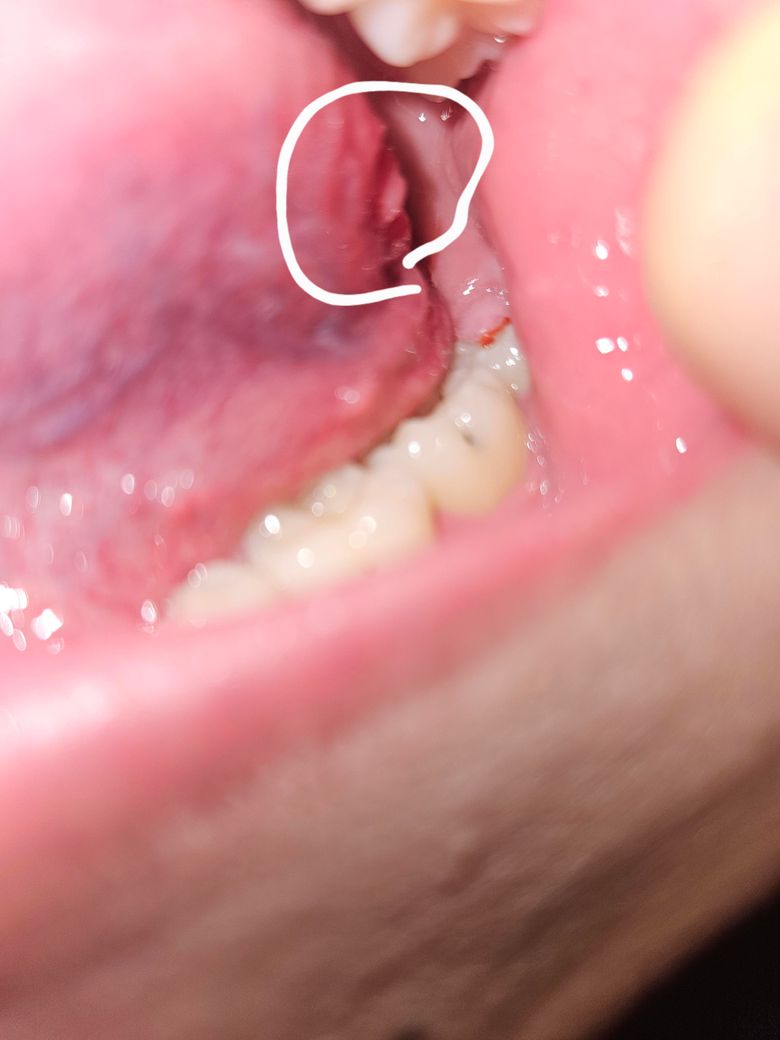

혀 안쪽 옆에 돌기가 생겼는데 근처에 통증이 있어요

혀 안쪽 사이드 부분에 이런 돌기같은게 생겼는데 이게 뭘까요. 최근 저 부분에 사랑니도 자라고 있어서 아픈데 혀도 같이 아픕니다..

최근 저 부분에 사랑니도 자라고 있어서 아프다면 씹으면서 생긴 상처일 것으로 예상됩니다.

혀에 자극이 가해지면 해당부위에 상처가 생기거나 돌기가 생길 수 있고 이 부분이 불편할 수 있습니다. 이런 경우 해당 부위를 자극하지 않는다면 증상이 줄어드는 경우가 많습니다.

자세한 확인을 위해서 치과에서 진료를 받아보는 것을 권유드립니다.

혀가 치아에 씹히면서 상처가 생긴거 같습니다. 최대한 자극이 가지 않도록 해주시는게 좋을것같습니다.

1. 구강 내 연조직 병소의 경우 사진만 보고는 정확한 판단이 어렵습니다 구강내과 내원해보시기 바랍니다

2. 단순 구내염일 경우 1~2주면 증상이 자연 개선되나 한달이상 지속된다면 종양관련 조직검사를 해보면 좋삽니다